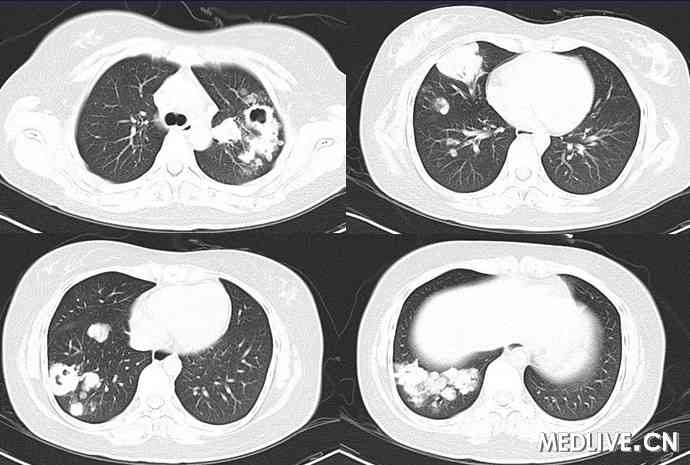

患者肺窗示右下肺可见占位性病变